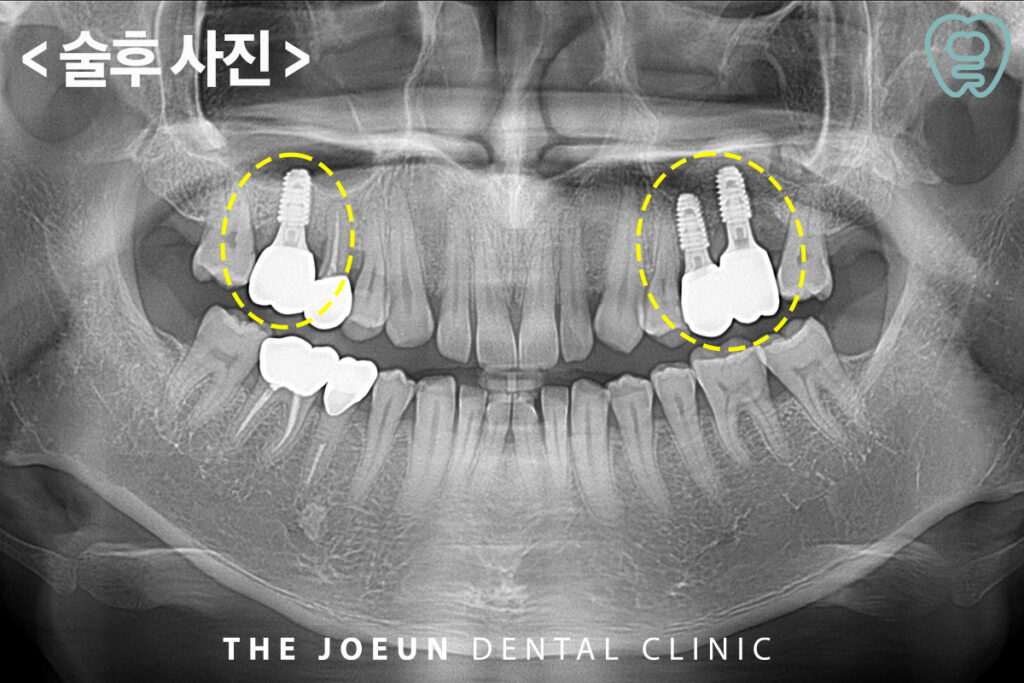

이어서 최종 6개월 후 왼쪽의 최종 보철물까지 완성하였습니다.

발치 후 즉시 임플란트를 진행할 때에는 식립에 앞서 반드시 계명대치과 정밀 검진을 통해 구강 상태를 면밀하게 확인하고 적합한 치료 계획을 세워야 합니다. 환자분의 불편함을 줄이고 완성도 높은 임플란트 치료를 하기 위해서는 치아 구조와 형태, 특징을 파악해 보철물을 디자인하는 것까지 꼼꼼히 진행되어야 합니다.